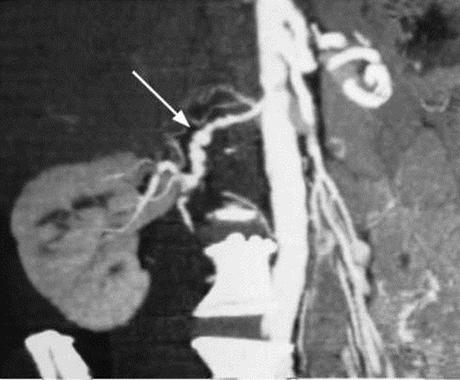

L'échographie Doppler des vaisseaux (image 35, voir l'onglet en couleur), le CT scan avec opacification (image 12.1) et l'IRM permettent de juger des dimensions du rein, de l'épaisseur de sa parenchyme, de l'état du système pyélo-caliciel et des vaisseaux rénaux.

La dysplasie fibromusculaire atteint les tiers moyen et distal de l'artère et se caractérise par une structure moniliforme (sous forme de fil de perles) (voir image 12.1). Le critère angiographique de la thrombose ou de l'embolie de l'artère rénale - c'est son amputation au niveau du tronc vasculaire principal. L'anévrisme de l'artère rénale se manifeste sous forme de protrusion sacciforme ou fusiforme de la paroi vasculaire.